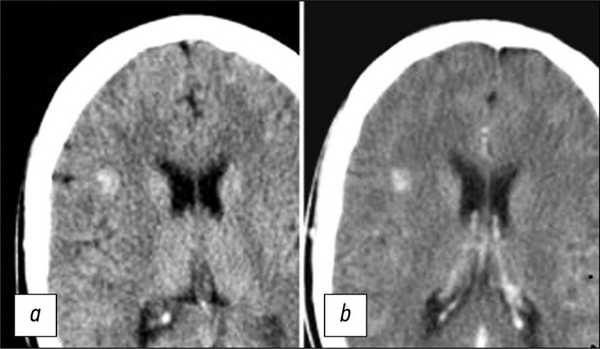

Использование КТ как единственного метода обнаружения КМ позволяет диагностировать очаги только в 30-50% случаев. Изображения, полученные при выполнении КТ, обычно демонстрируют наличие гиперденсных очагов, реже ― смешанных гипер- и изоденсных образований (рис. 1) [17]. КТ позволяет также выявлять признаки кальцификации очагов.

![]()

Рис. 1. КТ-срезы головного мозга в аксиальной плоскости, выполненные до- (a) и после введения контрастного препарата (b). На изображениях определяется гиперденсный очаг в правой лобной доле, без четких контуров, не накапливающий контрастный препарат.

Введение контрастного препарата способствовало улучшению определения границ КМ и повышению чувствительности в отношении выявления изоденсных очагов. Некоторые исследователи [18] предложили следующие признаки наличия КМ по результатам КТ: округлая форма, чётко определяемый край, неравномерная плотность, отсутствие окружающего отёка и эффекта массы (при отсутствии внутримозгового кровоизлияния). Тем не менее результаты КТ при диагностике КМ являются неспецифичными. Так, существенной проблемой является дифференциация КМ и частично кальцинированных аваскулярных глиом.